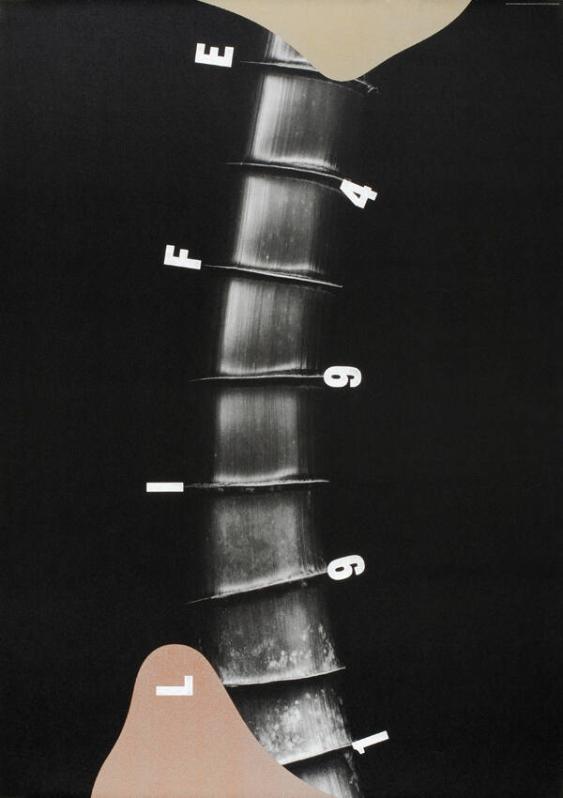

Plakat

Life 1994

1994

Design

Taku Satoh Design Office Inc., Tokio, JP

Taku Satoh

Photography

Megumu Wada

MediumOffset, Siebdruck

Dimensions103 × 73 cm

- Social Poster